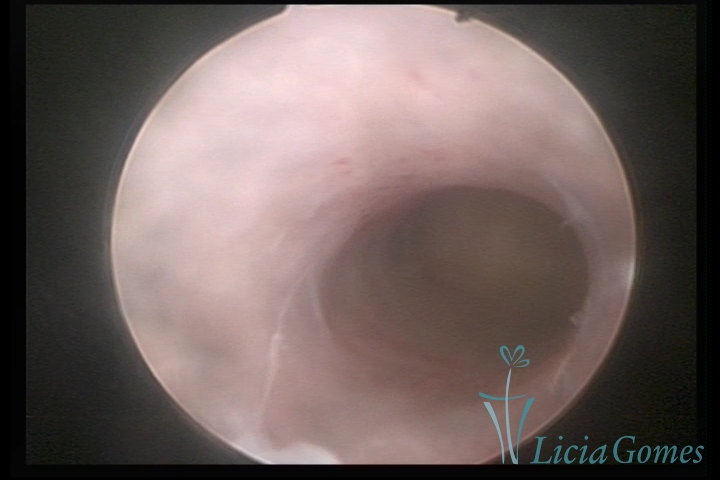

Terceira porção ou porção superior

Apresenta a mucosa com a superfície lisa e pouco vascularizada até a altura do orifício interno